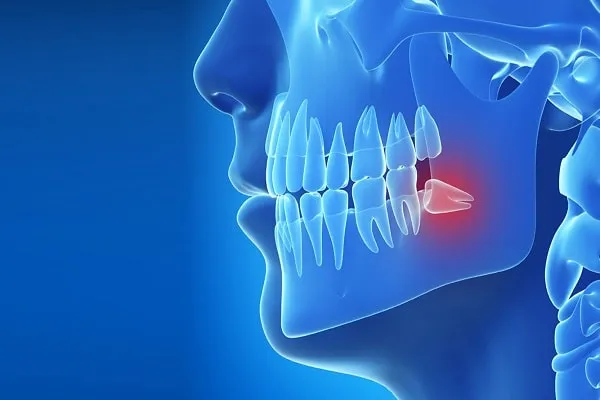

20’lik Dişin Çekilmemesi Ne Gibi Sorunlara Yol Açar?

20’lik Diş ve Erken Müdahale Önemi

Gömülü 20’lik Diş

20’lik Diş Çekimi Nasıl Yapılır?

20’lik Diş Neden Çekilir? Hangi Durumlarda Zorunludur?

20’lik Diş Nedir?